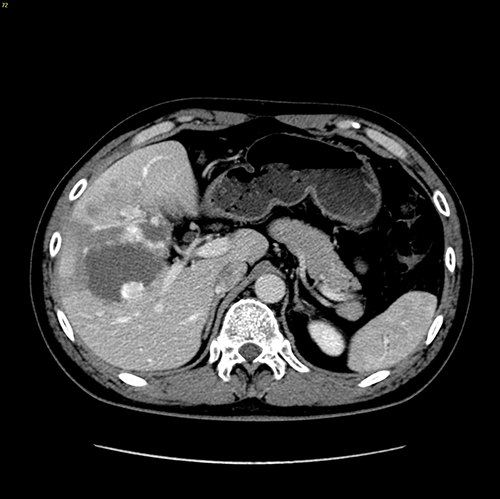

右肝巨大肝血管瘤---S56巨大肝血管瘤切除